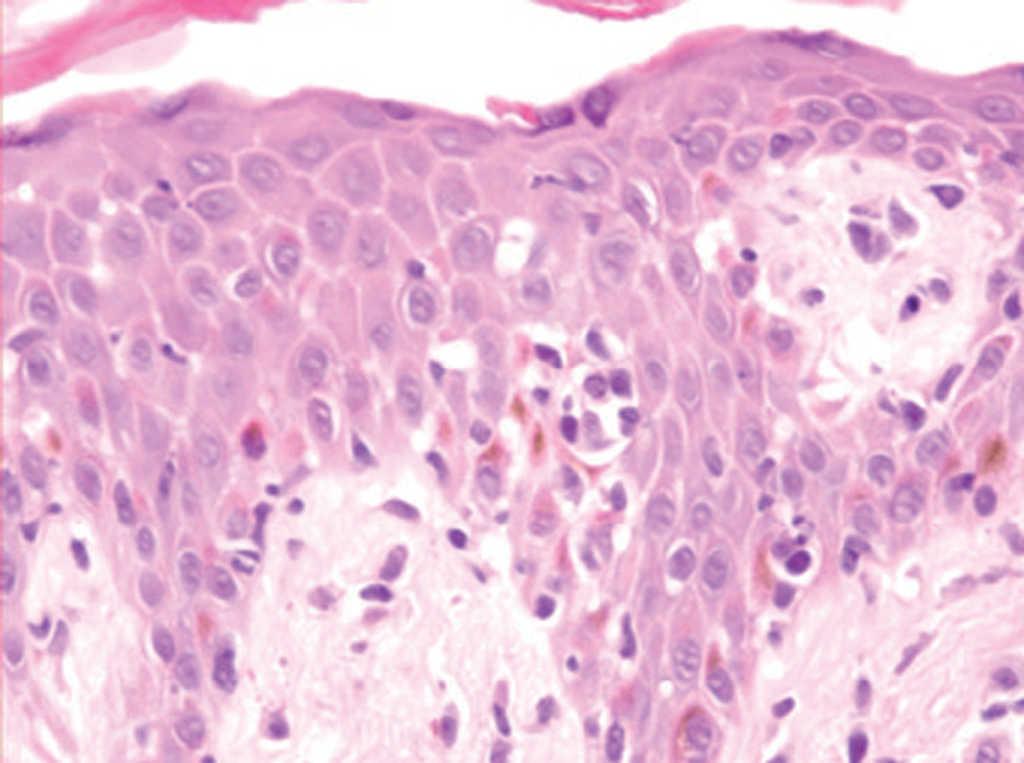

Una mujer de 42 años desarrolló múltiples lesiones maculopapulosas pruriginosas en el tronco y las extremidades 7 días después de iniciar un tratamiento con carbamazepina por una neuralgia del trigémino. A la exploración física presentaba lesiones maculopapulosas, eritematosas, no confluentes, bien limitadas con un diámetro aproximado de entre 0,5 y 2 cm en axilas, tronco, ingles y muslos (fig. 3). No presentaba adenopatías ni visceromegalias. La biopsia cutánea mostraba una epidermis con hiperqueratosis e hiperplasia psoriasiforme con un marcado epidermotropismo de linfocitos atípicos con núcleos hipercromáticos (fig. 4). No se pudo realizar el reordenamiento en piel por falta de material. Los análisis mostraron una hipercolesterolemia con ligera hipertransaminemia sin otras alteraciones. No se realizaron pruebas epicutáneas. Las lesiones se resolvieron en un mes sin tratamiento, tras a retirada de la carbamazepina.

Fig. 4.--Caso 2. Epidermotropismo de linfocitos atípicos de pequeño tamaño y microabscesos simulando una micosis fungoide. (Hematoxilina-eosina, x400.)

Nuestros pacientes tenían como hecho en común el patrón histológico tipo micosis fungoide. En el primer caso existía un denso infiltrado en banda de linfocitos pequeños en la dermis superficial con un epidermotropismo focal. Sin embargo, tanto en el segundo como en el tercer caso, se apreciaba mayor epidermotropismo con linfocitos atípicos de mayor tamaño y núcleo irregular que histológicamente recuerdan a la micosis fungoide.

Recientemente se ha realizado un estudio clinicopatológico y genotípico en 8 casos de seudolinfomas inducidos por anticonvulsivos 13. Las similitudes entre los seudolinfomas y las micosis fungoides fueron el epidermotropismo de linfocitos atípicos (100 %) y los microabscesos de Pautrier en el 38 %. Sin embargo, como hecho diferenciador en los seudolinfomas, existe una espongiosis que puede ser desde moderada a marcada (75 %), queratinocitos necróticos (63 %), infiltración de eosinófilos en la epidermis (25 %), edema de la dermis papilar (100 %), eritrocitos extravasados (100 %), linfocitos en la dermis mayores que aquellos que están en la epidermis (63 %) e infiltración de varias células inflamatorias incluyendo neutrófilos (50 %).